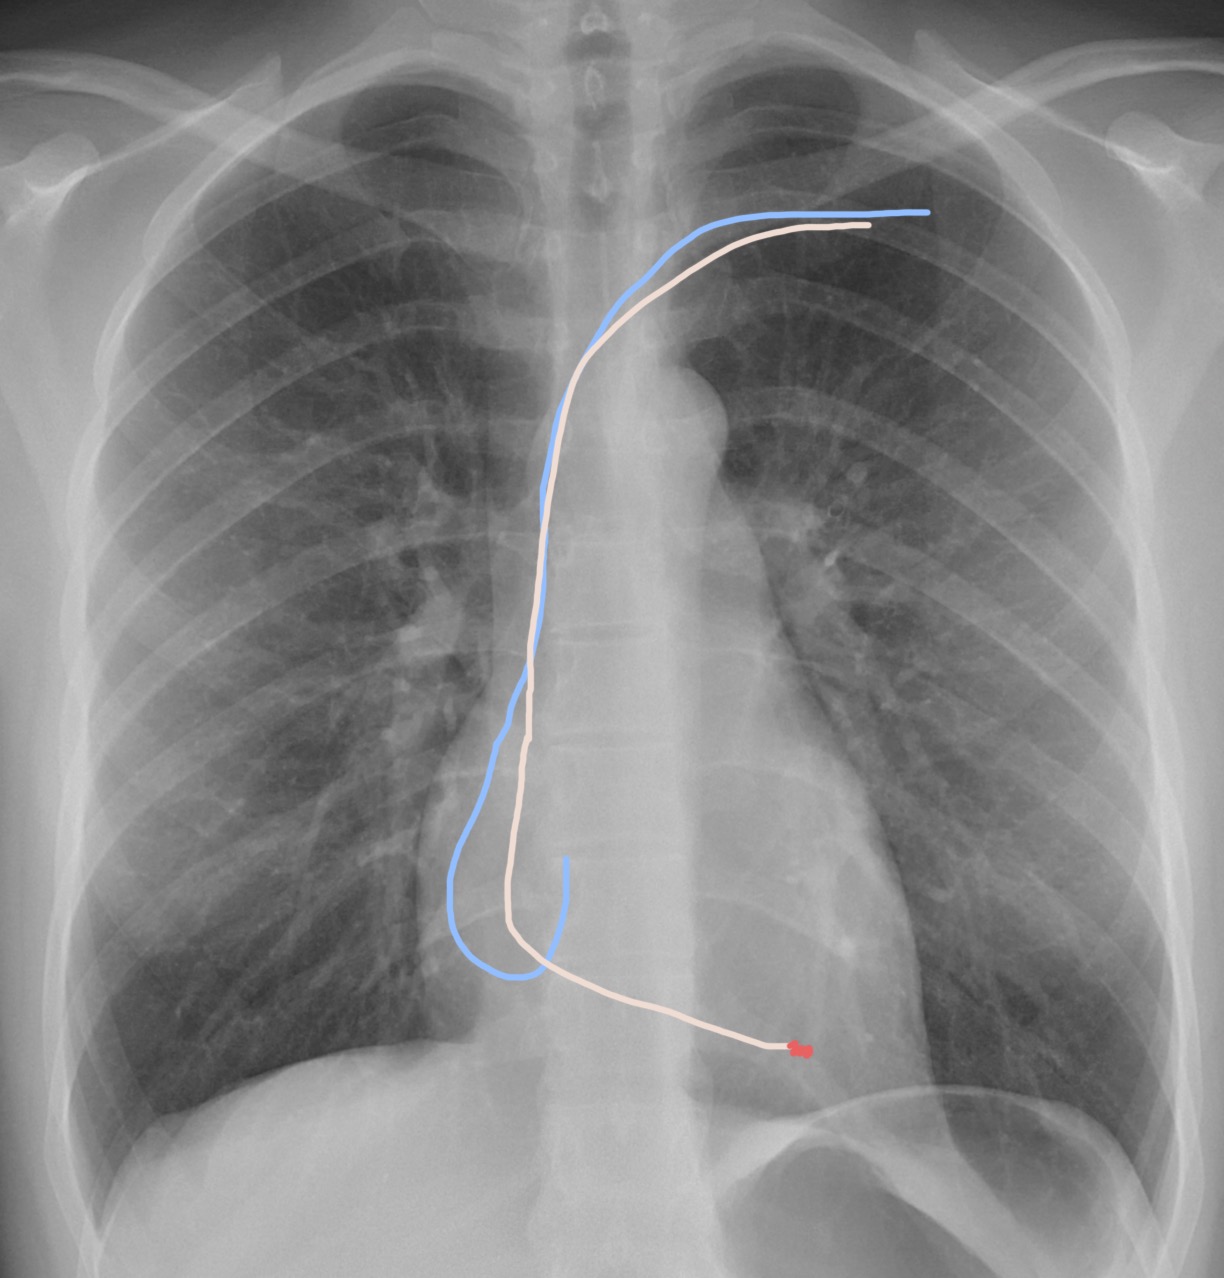

๐ŸŽฏ Step 20: Time for the atrial lead! ๐Ÿชก๐Ÿ’ซ

Now itโ€™s the atrial leadโ€™s turn. First, guide it into the inferior vena cava โฌ‡๏ธ๐Ÿซ, then introduce the dedicated atrial stylet๐ŸŽฉ.

๐ŸŽฃ Step 21: Hook the right atrial appendage! ๐Ÿชก๐Ÿ’ซ

With the atrial stylet, your lead will take on a hook shape.

๐Ÿ‘‰ The goal? To catch the right atrial appendage (RAA) ๐Ÿซ€ like a skilled fisherman reeling in the perfect catch ๐ŸŸ.